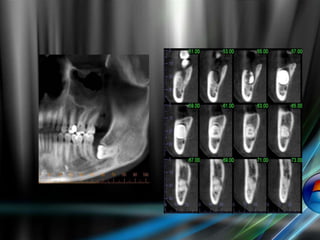

More accurate 3-D views of impacted teeth

 Provides more accurate 3-D views of

impacted molars, impacted cuspids, and other

supernumerary anomalies

 Visualize impaction within the alveolar bone,

location relative to adjacent teeth, and

proximity to vital structures

 More accurate information can result in less

invasive surgery/decreased surgical time

Radiography:

Dental x-rays confirm the presence of a tooth (or teeth)

that has not emerged.

Standard radiographic techs used to localize the

unerupted teeth, these include:

 Periapical films The tube shift method

 Occlusal films

 Panoramic view

 CT